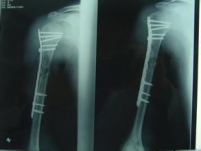

老年肱骨近端骨折---解剖髓內(nèi)支撐Endosteal anatomic support nail

老年女性,65歲,肱骨近端骨折,嚴(yán)重移位,骨質(zhì)疏松。如何使用解剖髓內(nèi)支撐技術(shù)獲得穩(wěn)定,允許早期功能鍛煉。視頻顯示解剖髓內(nèi)支撐治療老年肱骨近端骨折嚴(yán)重錯位,有效恢復(fù)肱骨近端解剖結(jié)構(gòu)。